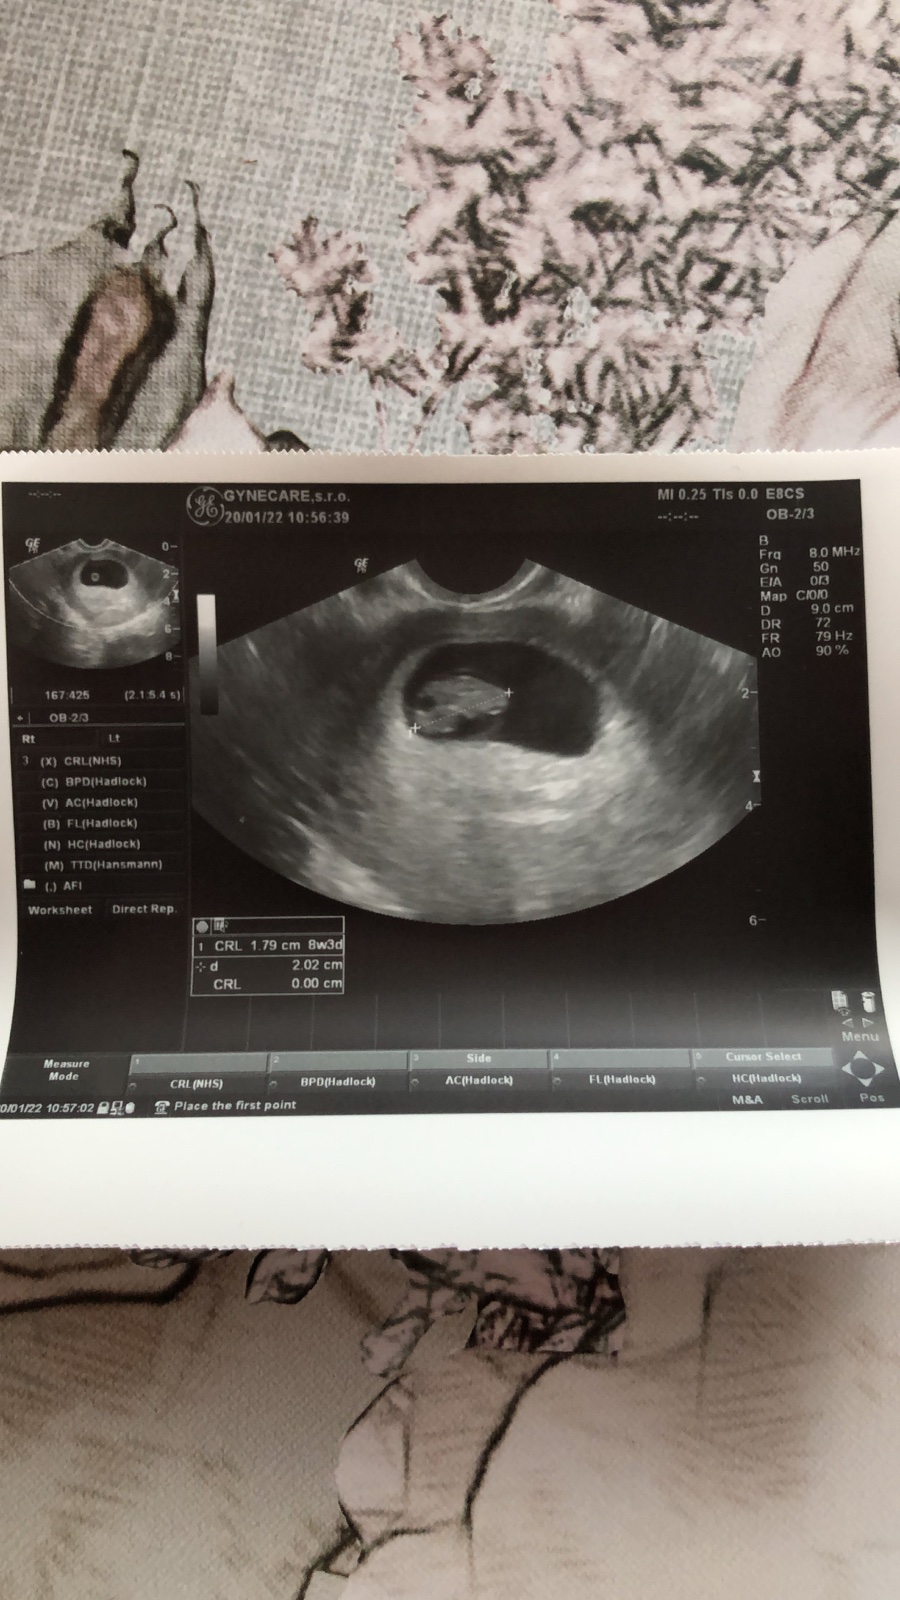

@zuzanaa2010 tu je mimi moje 🌸